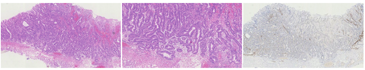

HE染色可见病变浅层有小凹上皮分布,深层可见不规则的、相互融合的腺体,且病变向深层延伸,突破黏膜肌层向下生长(图5)。17例病例完成了免疫组织化学染色,分别染色了代表分化为颈黏液细胞的Mucin-6、评估黏膜肌层侵犯的Desmin以及判断具体分型的Pepsinogen、H/K-ATPase(图6),部分病例还评估了增殖指数Ki-67及P53突变(图7)。

首先看分化情况,所有病例均有向颈黏液细胞分化的情况,其中7例有向小凹上皮分化的趋势。代表主细胞的Pepsinogen在所有病例中均为阳性,H/K-ATPase在4例病例中为阳性。该结果提示13例为主细胞型GA-FG,占76.5%;另外4例为混合细胞型GA-FG,占23.5%,未发现壁细胞型GA-FG。有15例病例完成了Ki-67染色,增殖水平均偏低。8例病例完成了P53突变染色,均为野生型(表3)。